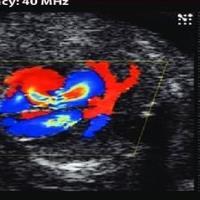

• سونوگرافی: یک روش تصویربرداری تشخیصی که با استفاده از امواج صوتی با فرکانس بالا انجام می‌شود.